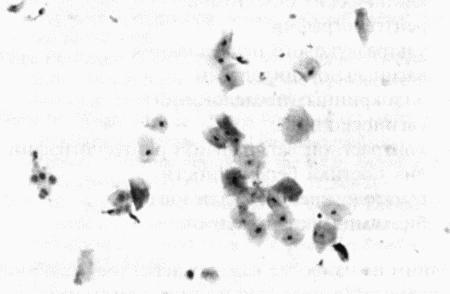

Фиг. 4.5.

Вагинальная цитология суки с кистами яичников. Проэструс начался 34 дня назад. Выделения типичны для конца проэструса и содержат поверхностные клетки (см. Приложение)